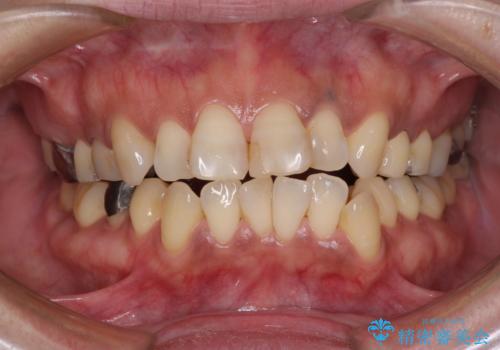

- 何度もコンポジットレジンによる修復を繰り返した結果、冷たいものがしみるようになってしまったとのことで来院された患者様です。

前歯2本が捻れている形態も気になるとのことであったので、虫歯の治療を兼ねて、オールセラミッククラウンにて補綴治療を行うこととしました。

2本とも治療前の歯髄の状態は正常でしたが、補綴治療により歯を大きく削ることになるため、歯髄が炎症を起こすリスクがあることを了解いただきました。

色彩や形態が大きく改善されたことはもちろん、虫歯によってしみていた症状もなくなり、患者様には大変満足していただきました。